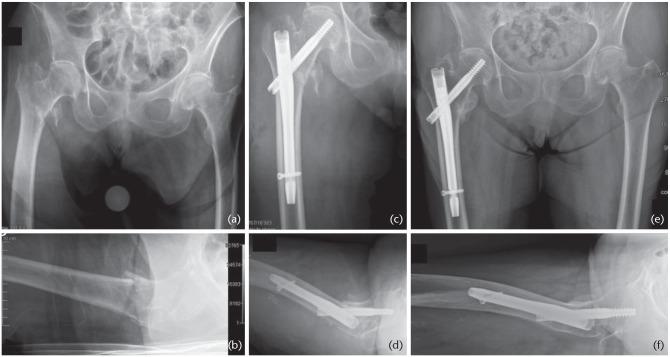

股骨转子间骨折常采用四孔侧板滑动髋螺钉装置固定,但近几十年来,人们尝试使用两孔侧板以尽量减少手术时间、手术切口、失血和术后疼痛。本综述的目的是确定两孔滑动髋螺钉结构是否是治疗AO-OTA 31-A1和A2型股骨转子间骨折的可接受选择。使用PubMed®对电子MEDLINE®数据库进行检索,如果文章报道了使用两孔滑动髋螺钉装置进行转子间骨折固定的历史、生物力学、临床或结果数据,则纳入本综述。对于AO-OTA 31-A1型单纯转子间骨折的固定,推荐采用两孔动力髋螺钉结合微创肌肉劈开入路;这种植入物在生物力学上是安全的,并允许采用微创肌肉劈开入路,这可能会带来更好的临床效果,如减少手术创伤、缩短手术时间、减少失血、减少镇痛药物使用和缩短切口长度。由于大多数综述文献都与动力髋螺钉有关,因此尚不清楚上述建议是否可扩展到任何其他滑动髋螺钉装置。对于所有其他囊外近端股骨骨折,推荐使用髓内装置。引用本文:2020;5:118-125。DOI:10.1302/2058-5241.5.190020。

https://cdn.ncbi.nlm.nih.gov/pmc/blobs/770a/7047904/d8a8d2a99165/eor-5-118-g003.jpg

https://cdn.ncbi.nlm.nih.gov/pmc/blobs/770a/7047904/5e8fe7692d64/eor-5-118-g001.jpg

https://cdn.ncbi.nlm.nih.gov/pmc/blobs/770a/7047904/7137cea077d5/eor-5-118-g002.jpg